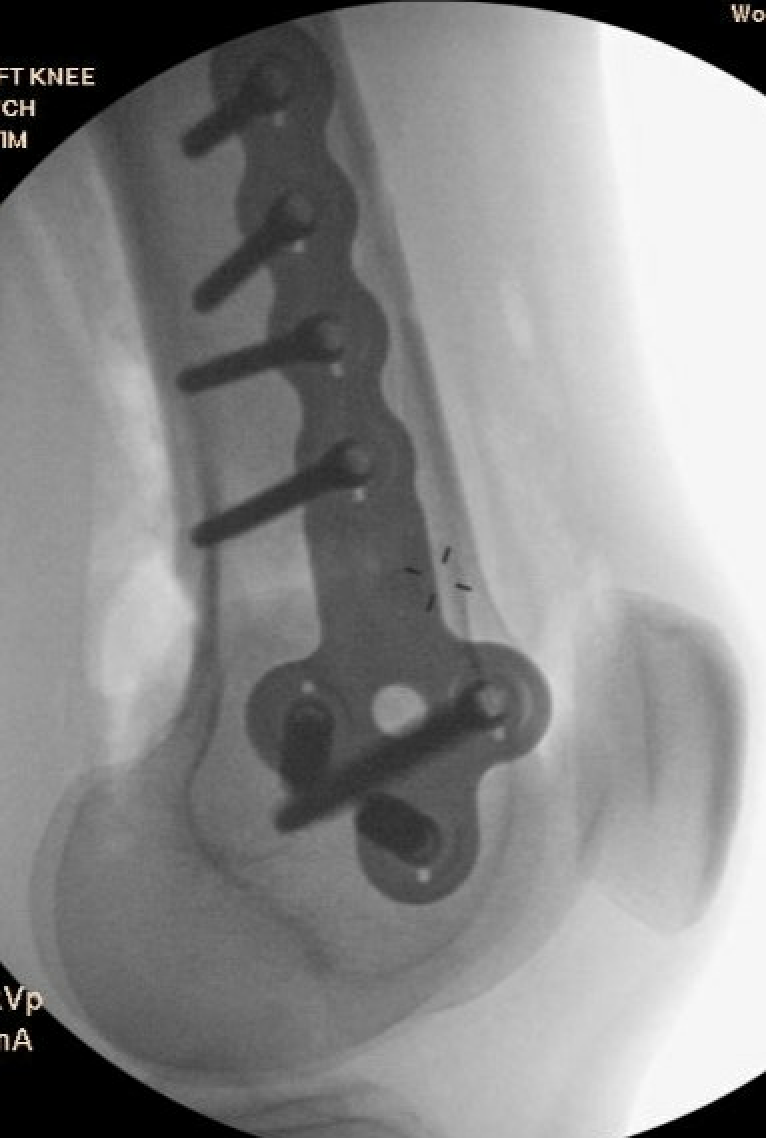

Distal Femoral Osteotomy Guide wireDistal Femoral Osteotomy Puddhu PlateLateral Distal Femoral Osteotomy

Technique

Arthrex ContourLock Distal Femoral Osteotomy Plates

Patient supine on a radiolucent table

Surgical approach

- lateral 12 - 15 cm incision

- split iliotibial band

- ligate perforators and elevate vastus lateralis off intermuscular septum anteriorly

- release intermuscular septum posteriorly at metaphyseal-diaphyseal junction

- protect neurovascular bundle

OW DFVO 1OW DFVO 2

Osteotomy

- insert guide wires

- proximal lateral to distal medial

- proximal 1 - 2 cm above flare of lateral condyle

- aim towards adductor tubercle

- risk of medial hinge fracture reduced if osteotomy at or distal to adductor tubercle

- ensure these are perpendicular to the femoral shaft in the sagittal plane

- above patellofemoral joint and posterior condyles

- stop osteotomy 1 cm short of medial cortex

Open osteotomy

- maintain medial cortical hinge

- limit opening wedge to reduce fracture risk

Distal femoral locking plate + bone graft